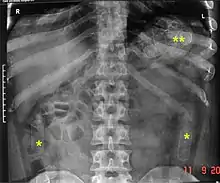

Routine detection of the smuggled packets is extremely difficult, and many cases come to light because a packet has ruptured or because of intestinal obstruction. Unruptured packets may sometimes be detected by rectal or vaginal examination, but the only reliable way is by X-ray of the abdomen. Hashish appears denser than stool, cocaine is approximately the same density as stool, while heroin looks like air.[11][12]

Dx by: Abdominal radiograph, physical evidence of packet, exploratory laparotomy to remove additional packets, sigmoidoscopy.... These were found INSIDE the patient's bowel.... Cocaine packets recovered in the Emergency Department from rectal cavity of patient. Cocaine is stuffed into latex glove fingers and tied. Condoms may also be used - but are more expensive.